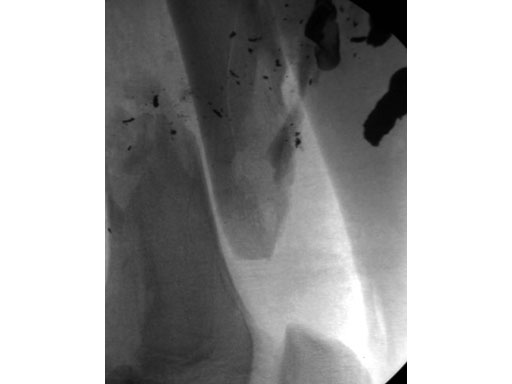

After stabilizing the fracture with an intramedullary nail (Fig 2) the patient was mobilized with weight bearing as tolerated. Uneventful healing and range of motion of the knee and functional ambulation returned to normal. Alignment of the fracture has been maintained with healing and maturation of callus processing as predicted. Blood supply to the proximal femur has been reserved with no signs of avascular necrosis. The ALFN's lateral entry point makes the nail insertion safer and diminishes the risk of circumflex artery injury.

Fig 2 Immediate postoperative AP x-ray.